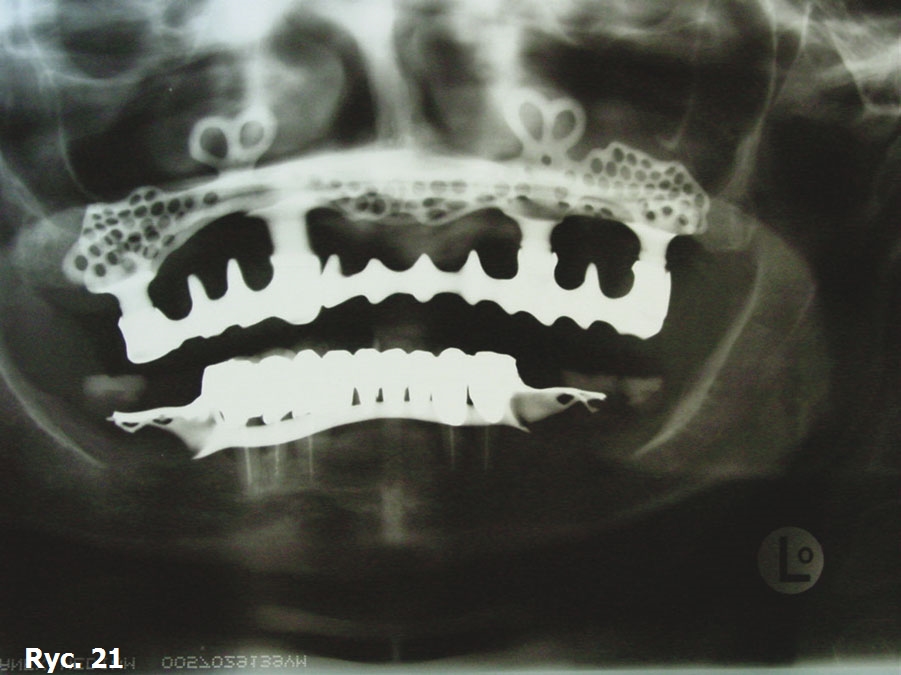

Obrazy TK oraz modele stereolitograficzne ukazują wysoki stopień zaniku tkanek twardych szczęki. Z tego powodu wykonano projekt wszczepu podokostnowego full arch (ryc. 14), który odlano z 5. gatunku tytanu (ryc. 15) i wszczepiono. Zabieg odbył się bez powikłań (ryc. 16). Leczenie zakończyło się wykonaniem i oddaniem protezy stałej full arch typu all on four, która w pełni zaspokaja estetyczne oraz funcjonalne oczekiwania pacjentki (ryc. 17, 18, 19, 20, 21).

Wszczepy podokostnowe - przypadek 3 (ryciny)